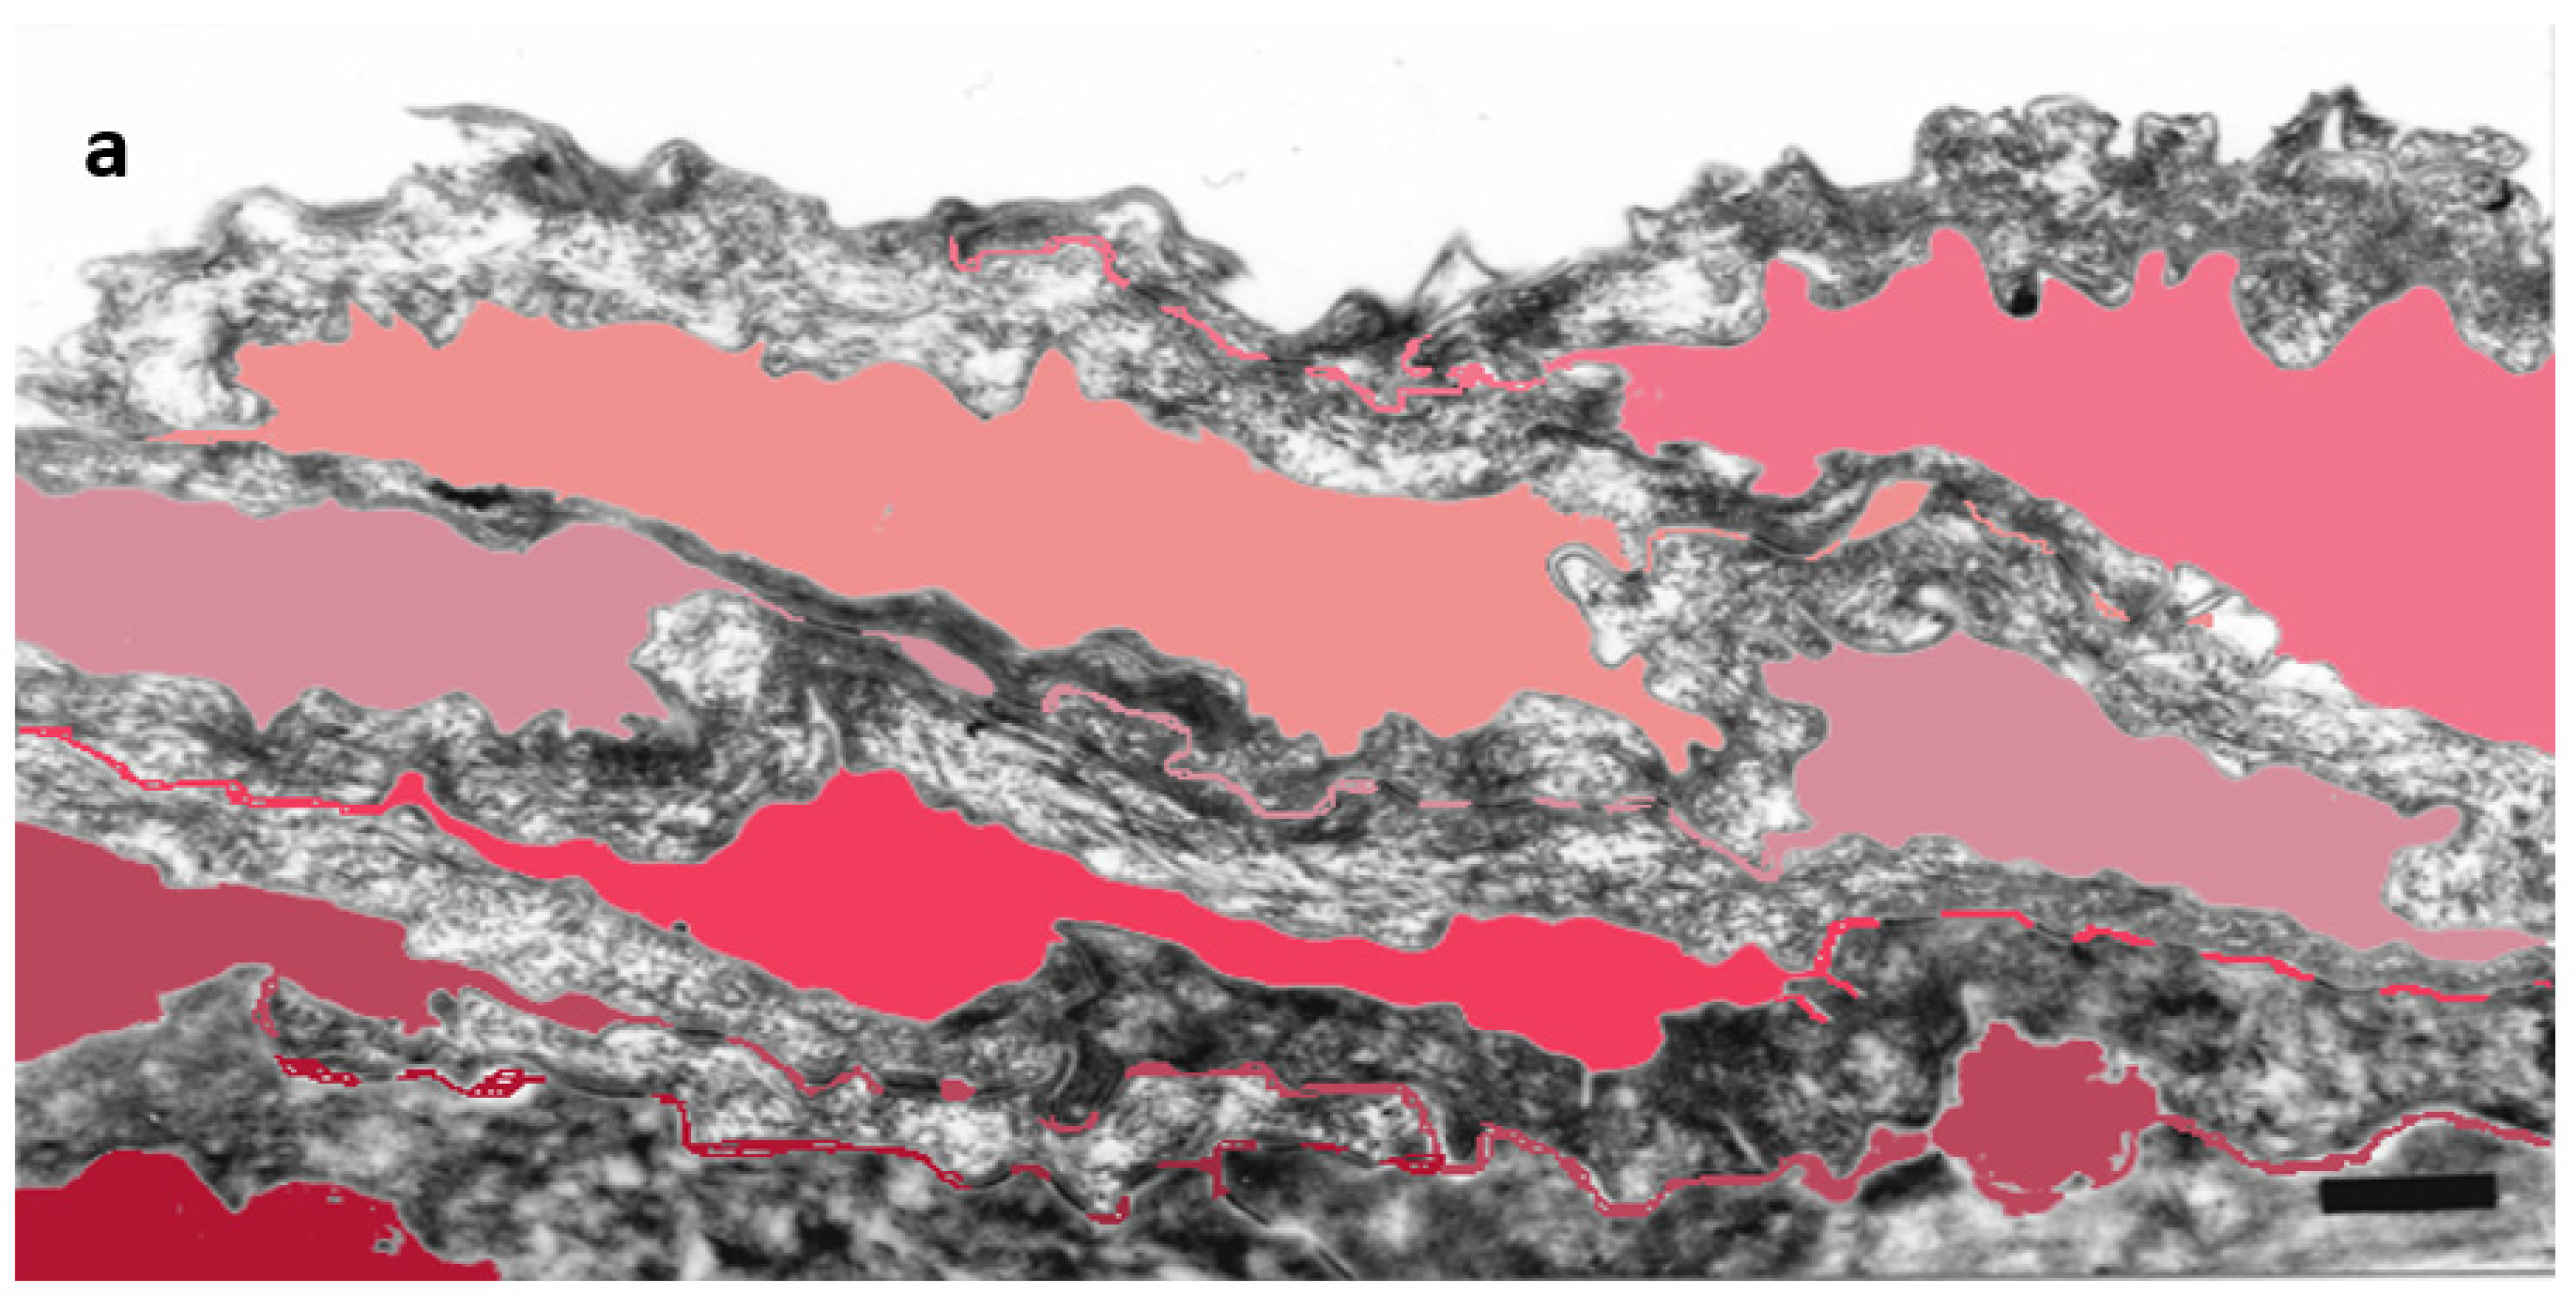

Detailed ultrastructural observations confirmed that TJ-derived points of contact persist in the SC (Figure 1) and can be quantified (Table 1).

Figure 1.

Subdivision of the extracellular space of SC into separate compartments, (a) indicated in different colors; (b) apical-lateral TJ remnants (arrows) intercalating corneodesmosomes (d) may be quantified; (c) an example of “closed” and “open” apical-lateral contacts between the three SC 2 corneocytes. TJ-derived fusions of corneocyte envelopes seal the extracellular space (*). Bar in (a) = 1 µm; in (b,c) = 200 nm.